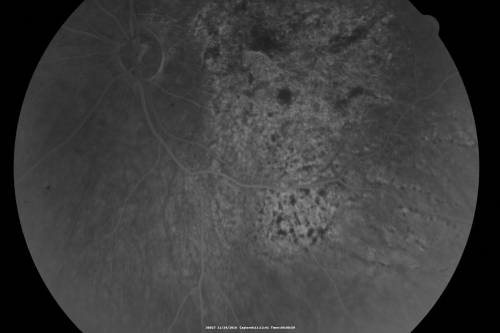

Pistol to head in attempted suicide 3 Months Ago - Retinal Atrophy - Shockwave Retinopathy VA Right Eye - Light Perception - Left Eye - 20/400

66-year-old woman had a gunshot wound to the head on August 12, 2010, with the entry wound just on the right side, just about below her temple, toward the lower part of the temple and the exit wound on the left side just above her cheek, a little behind the eye.  Since then she recovered and did not need any surgery.  When that all cleared she realized her vision was poor in both eyes.  She has seen a neuro-ophthalmologist who thought she had traumatic optic neuropathy.   OD light perception, OS 20/400.